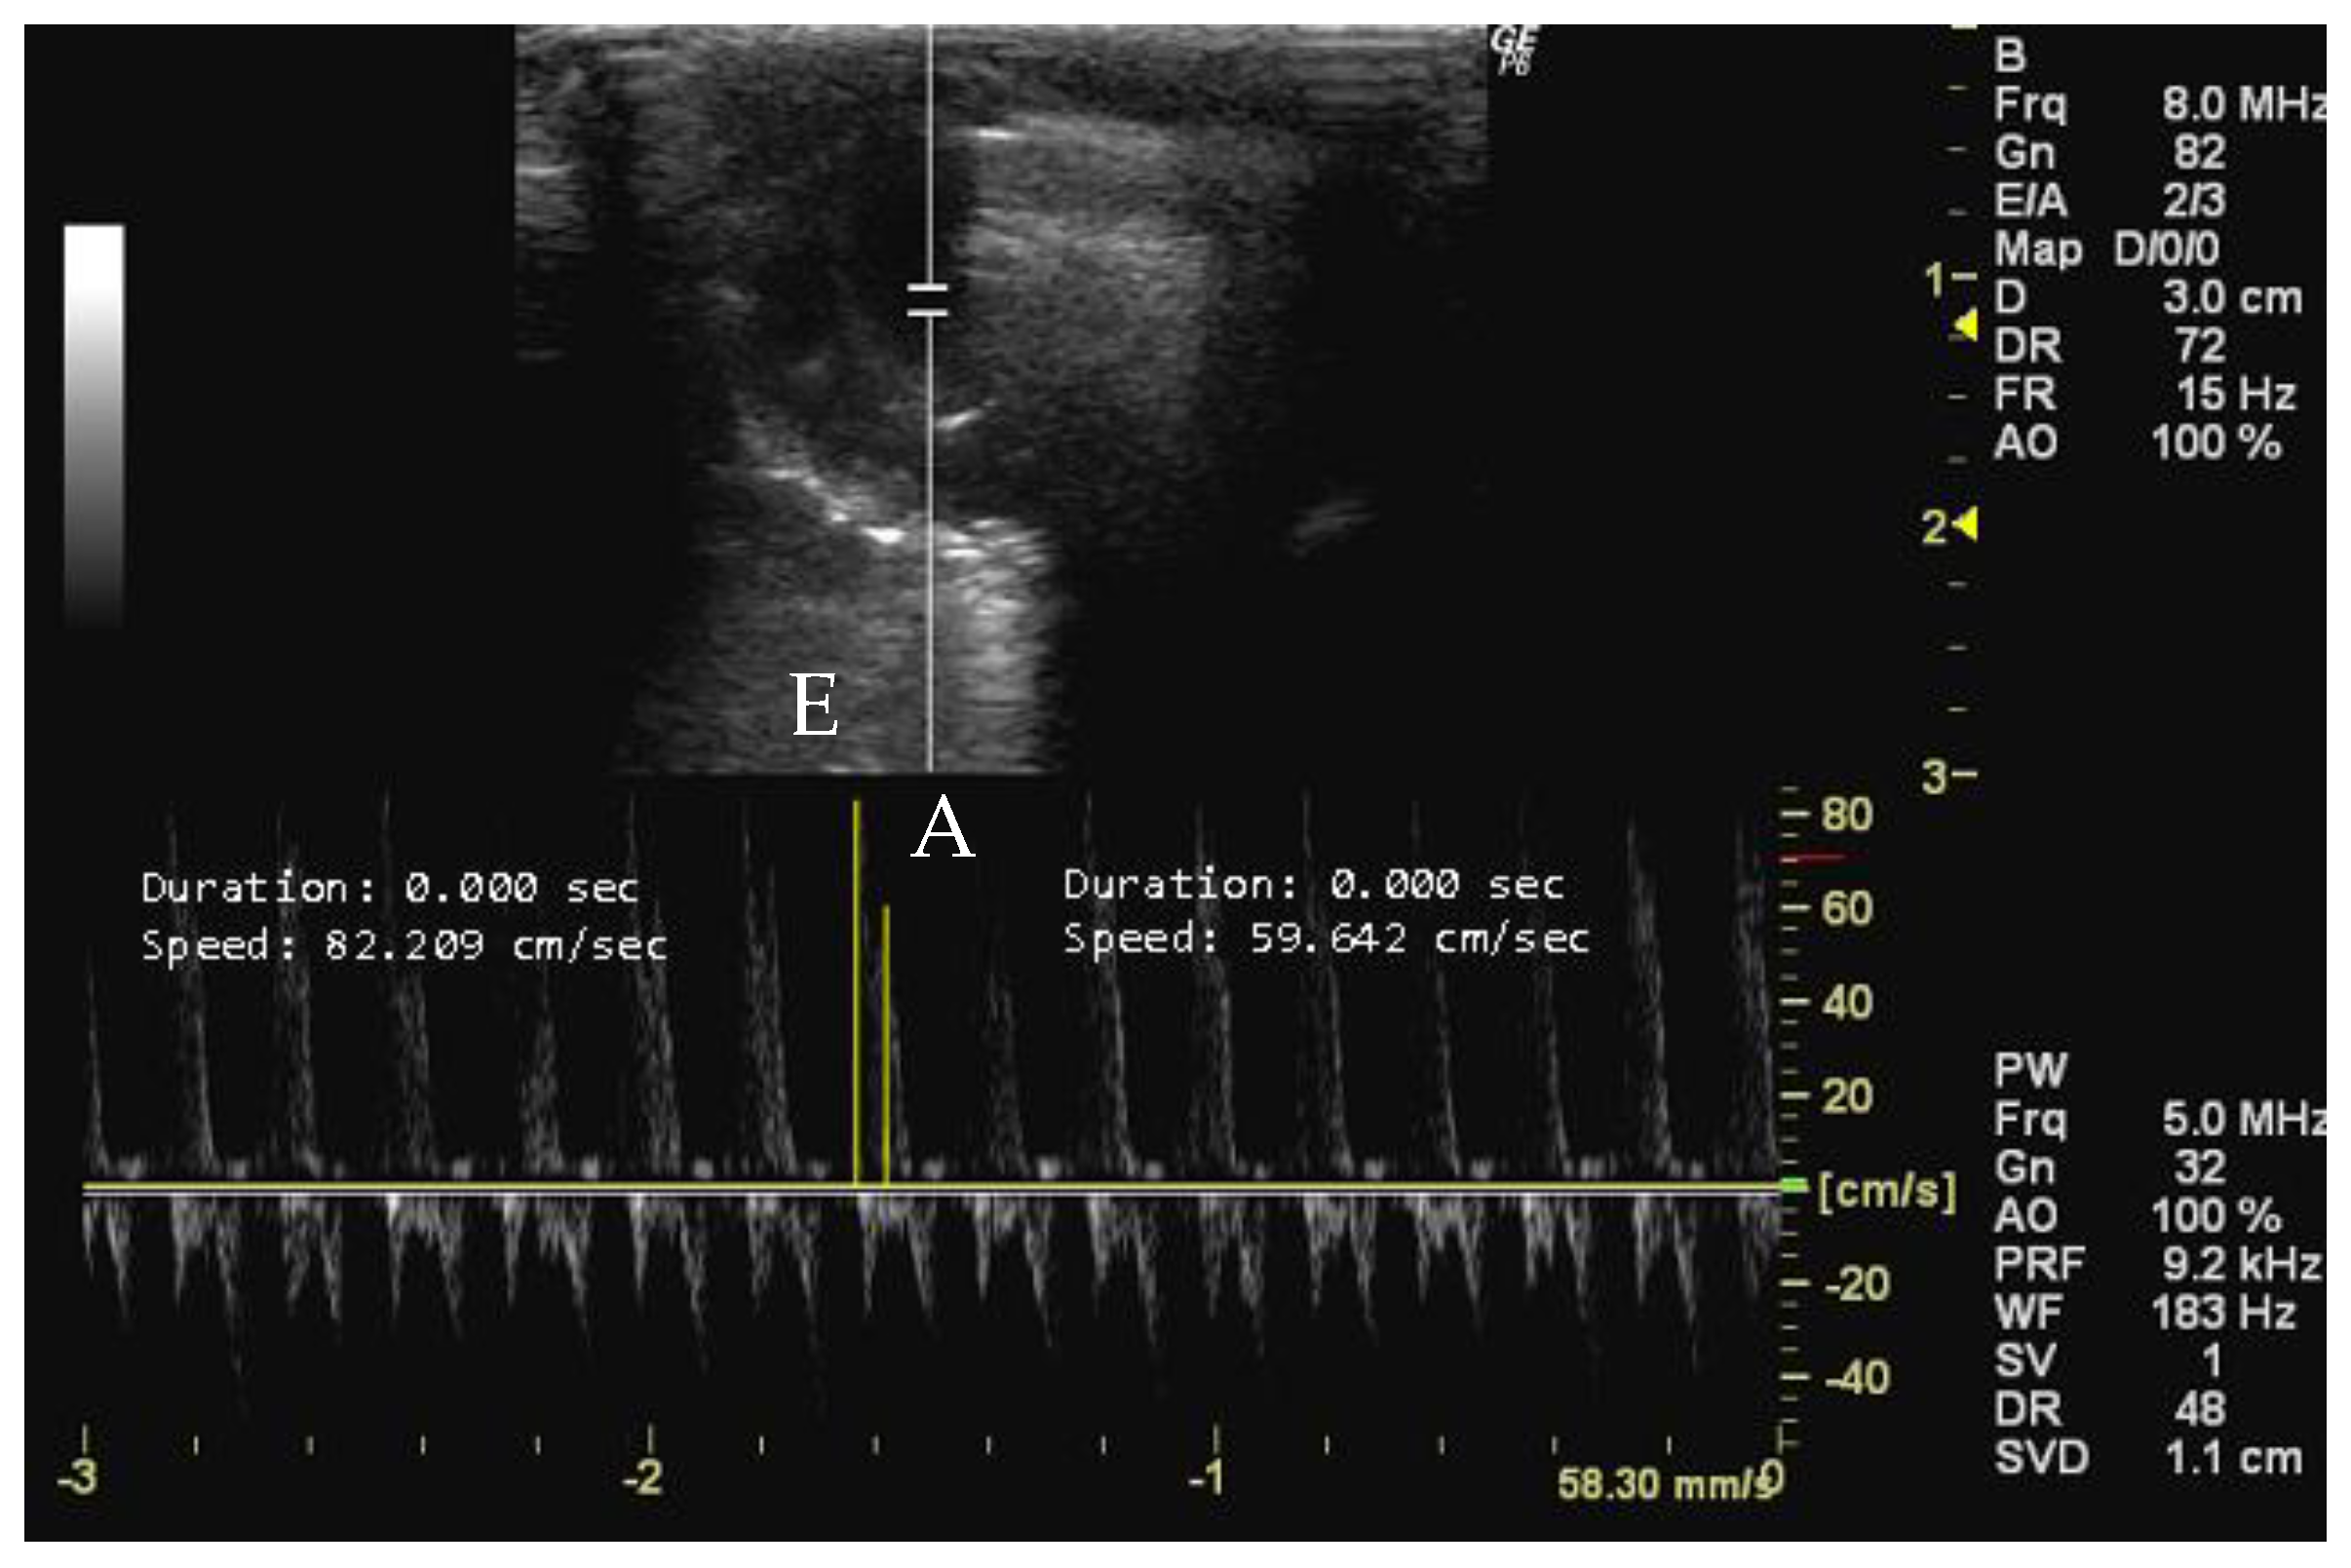

- How to measure E and A peaks